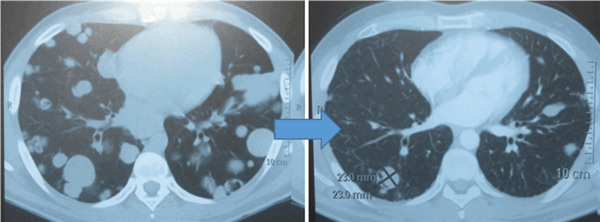

![Метастазы в легких до лечения и после 4х циклов химиотерапии по схеме «ВЕР» (КТ грудной клетки)]()

Метастазы в легких до лечения и после 4х циклов химиотерапии по схеме «ВЕР» (КТ грудной клетки)